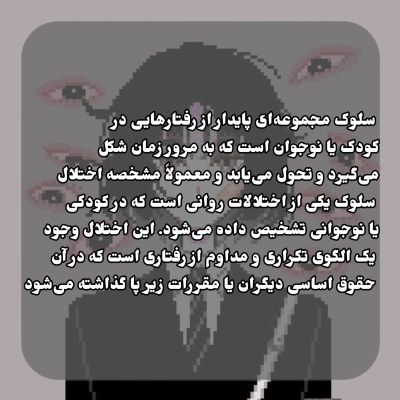

معرفی اختلال سلوک؛ اختلالی در رابطه با رفتار پرخاشگرانه کودکان و نوجوانان.